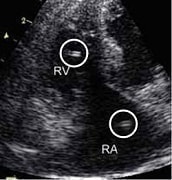

検査法④ エコー検査

フィラリアがいるとエコーで『=』のように見え、検出率の高い検査です。

※心臓内のフィラリアしか発見できません。ネコちゃんでは、心臓以外(肺など)にいるフィラリアが症状を起こして問題となることが一般的です。